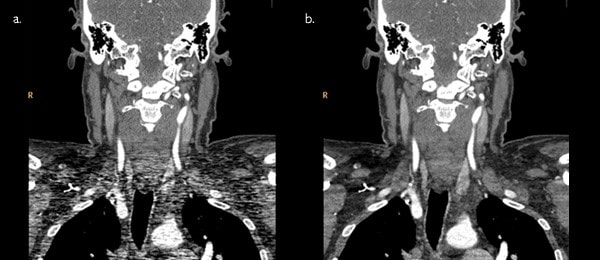

Сравнение двух снимков: слева – без включения iDose4, справа – с активной функцией.